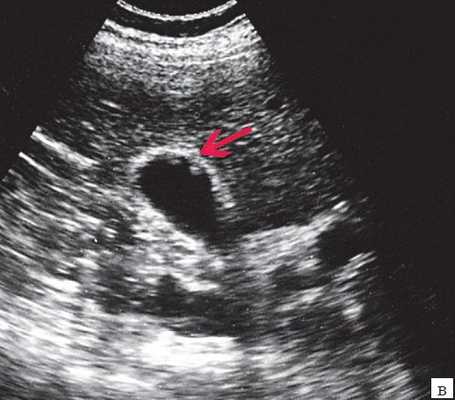

(Левый) На продольном УЗ срезе визуализируется желчный пузырь, содержащий не отбрасывающий тени опухолевидный сладж.

(Правый) Положение пациента на боку. На продольном срезе в просвете желчного пузыря определяются подвижные множественные флотирующие эхо-сигналы. Обратите внимание на почти спавшийся желчный пузырь и выраженное утолщение его стенки.